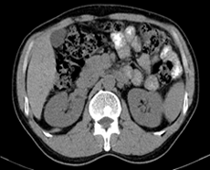

患者,男,57,常年不吃午饭,近一个月来腹部隐痛,无明显黄疸,明天进行增强扫描,图象另上传,麻烦各位帮忙一起看看讨论讨论

肝外胆管扩张,胰头增大,肠系膜上静脉似有包埋征象。

考虑:胰头占位性病变,建议增强进一步检查。

肝外胆管扩张,胰头增大,占位性病变可能性大.

胰头增大,考虑胰头占位性病变。

胰头增大,胆总管增宽,考虑胰头癌可能性大,明天看增强片有助诊断.